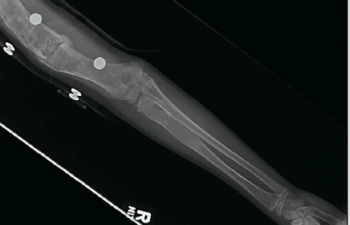

A 15-year-old adolescent Caucasian male with no significant past medical history presented to the clinic with gradually worsening left ankle pain over the past 2 weeks, ever since he started his football practice. He complained of dull aching pain at the lower end of his left leg for the past 4 months, which was slightly relieved by over-the-counter nonsteroidal anti-inflammatory drugs (NSAIDs). He twisted his left ankle and noticed further worsening pain, which prompted this doctor visit.